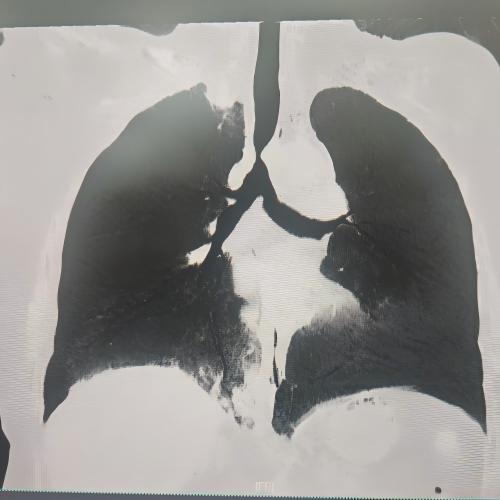

患者为75岁女性,因“反复咳嗽咳痰、气促10余年,加重3月”,于3月3日入住湘雅三医院呼吸与危重症医学科。入院时患者呼吸困难症状严重,CT检查提示气道存在严重狭窄,随时面临窒息风险。经管床医生杨红辉评估,患者气管狭窄情况复杂:最狭窄处管腔直径仅剩1-3mm,科室最细的4.0mm支气管镜也无法通过;狭窄位置极低,下缘距隆突仅1.6cm,意味着无法通过气管切开绕过病灶;狭窄处周围组织的CT值高达60-70Hu且无强化,因而直接植入支架存在无法撑开或加重堵塞的风险;同时,患者无法耐受全身麻醉,仅能采用利多卡因进行表面麻醉,操作难度较大。

方案确定后,ICU团队何智辉、邢伟、邓龙天为患者建立体外生命通道;呼吸介入团队孟婕、杨红辉、刘建明、邹丽君、贺一峻等通过球囊对狭窄部位进行预扩张,随后在距隆突仅1.6cm的低位气道精准植入支架。支架贴合良好,气道顺利开通,全程操作约1.5小时。患者当晚撤离ECMO,次日从ICU转回普通病房。后续肺泡灌洗液检测显示,患者大气道狭窄的原因为气管结核导致的瘢痕性狭窄。